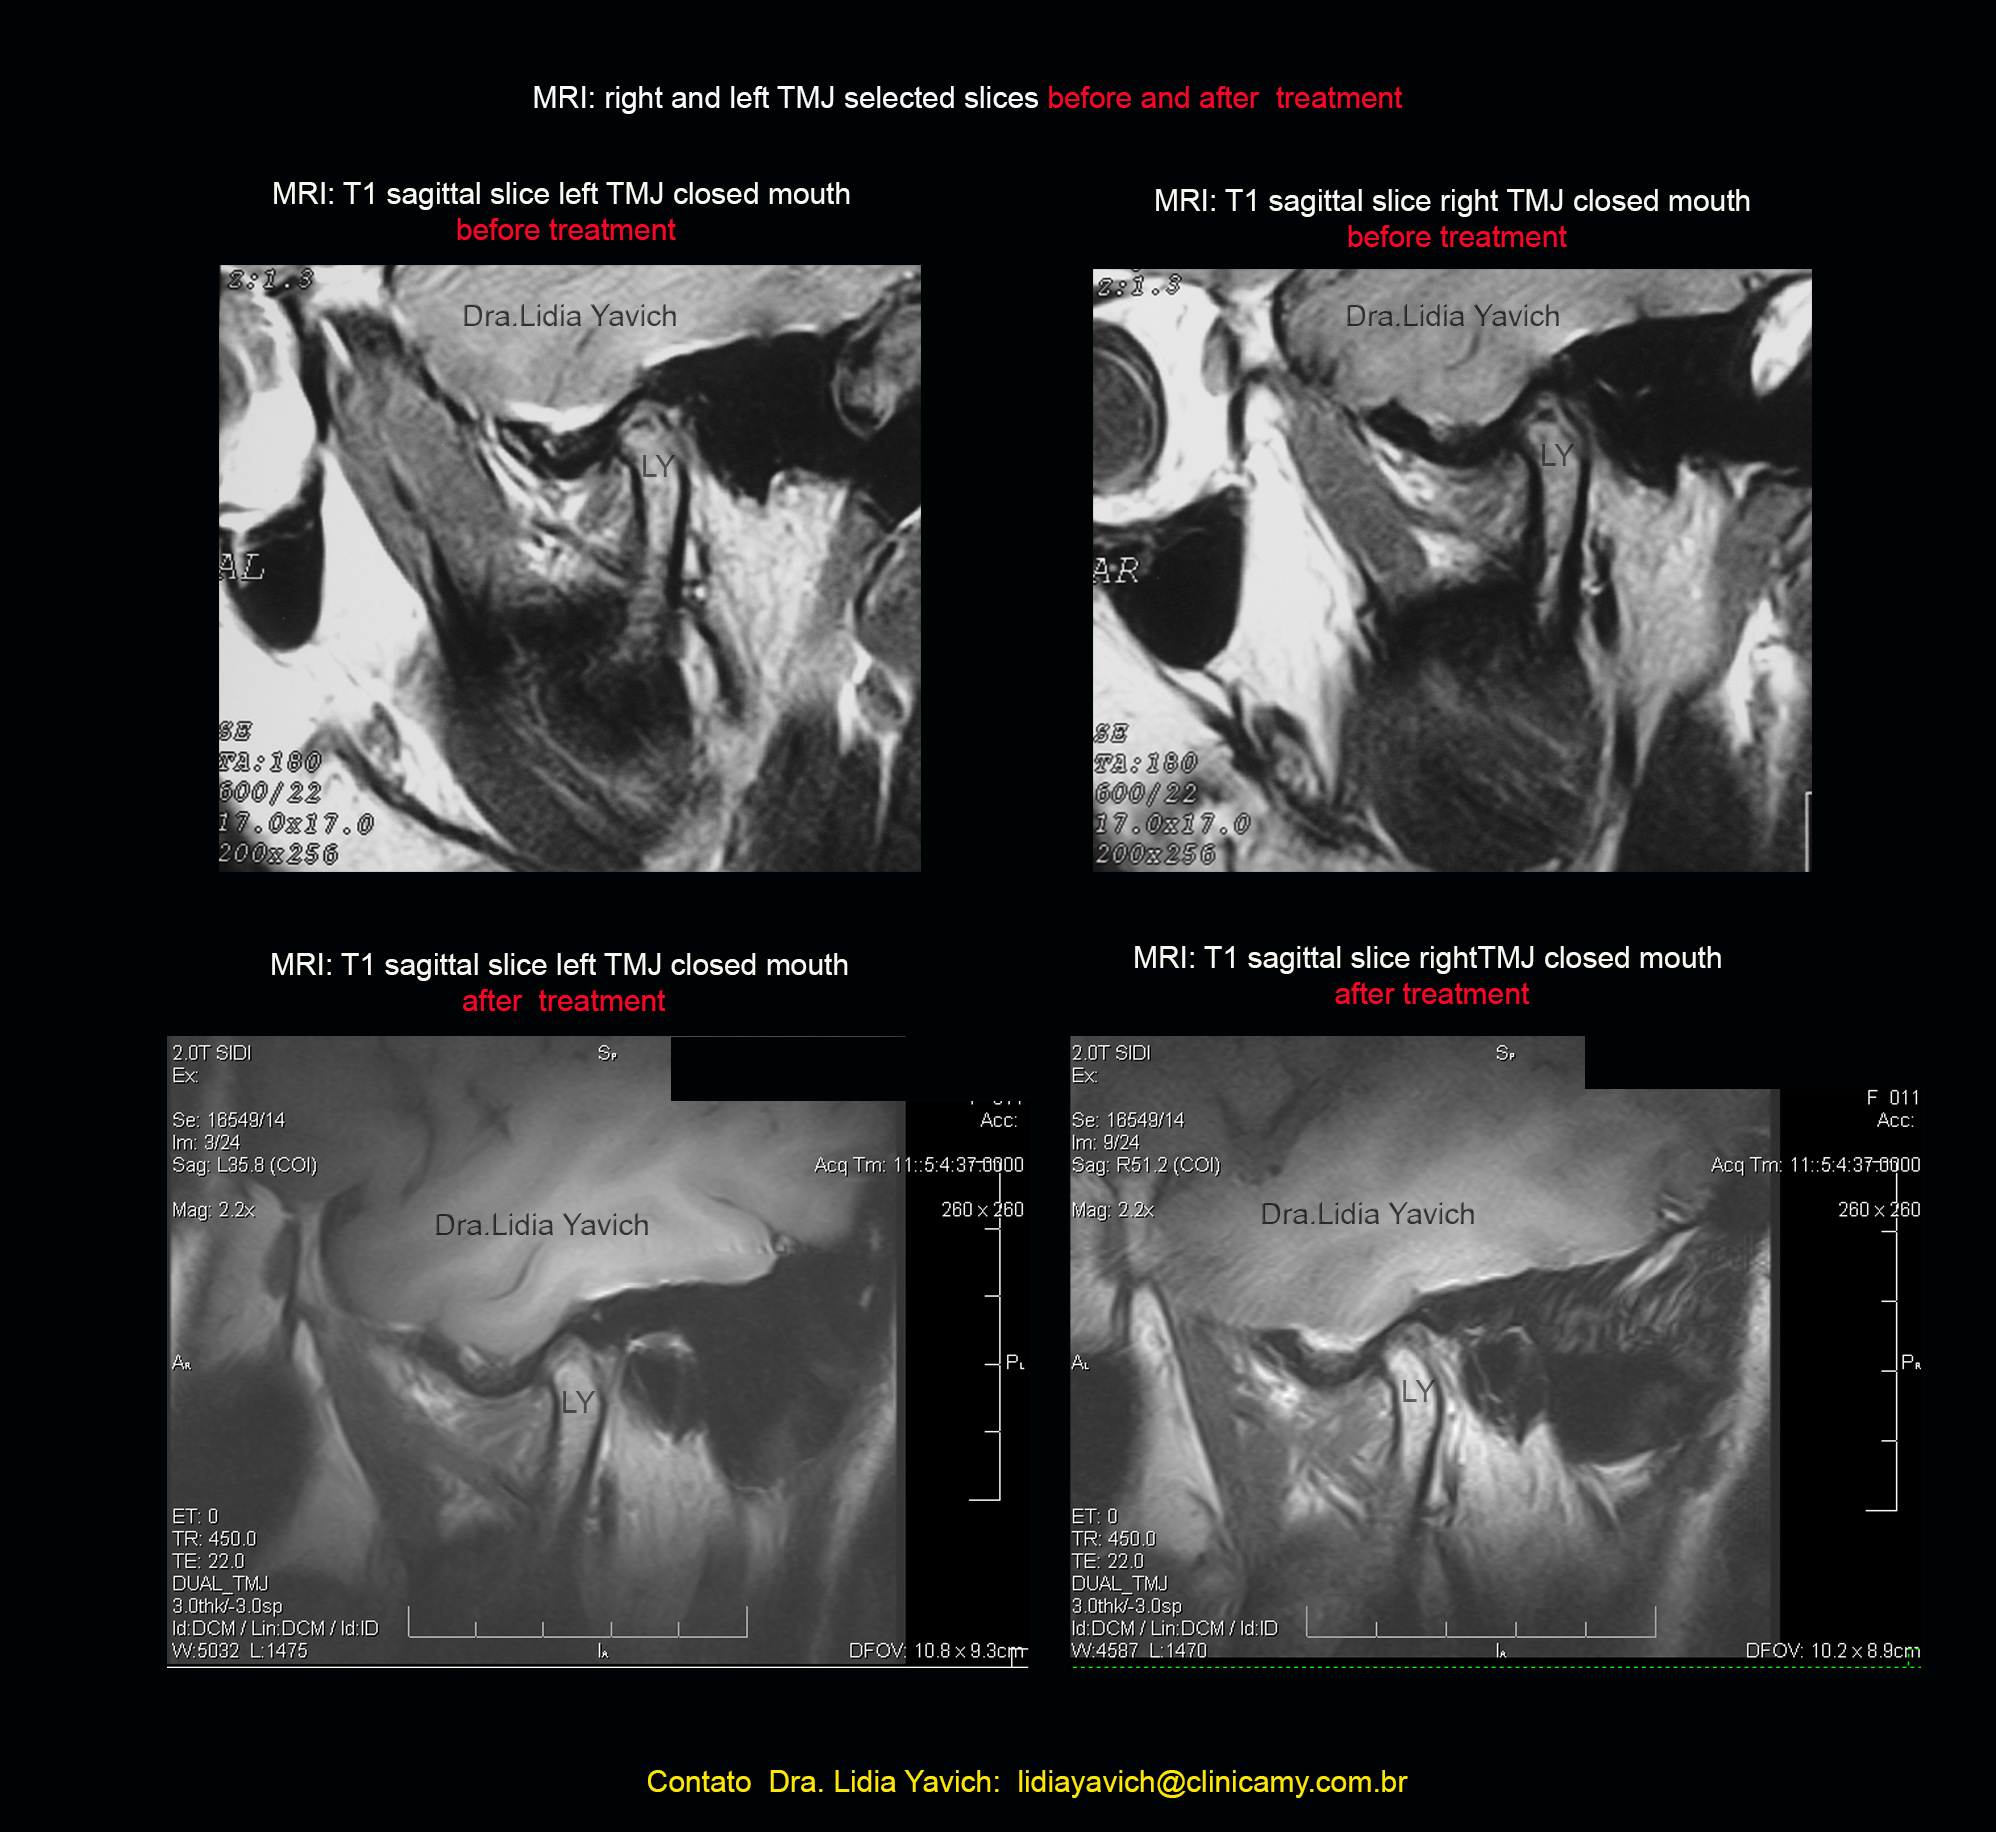

Na ressonância nuclear magnética observa-se angulação anterior dos processos articulares, aplainamento da superfície superior e posterior de ambos os processos articulares. Informação que tínhamos na laminografia.

Os discos articulares estão afilados o que implica estruturalmente um disco que nem sempre pode cumprir a função para o que um disco está desenhado. De tudo jeito é imperativo promover uma descompressão articular.

RNM (ressonância nuclear magnética) comparativas da paciente em oclusão habitual antes do tratamento e em oclusão neurofisiológica na finalização do tratamento.

Deve ser compreendido que a posição mandibular escolhida é aquela onde as articulações estejam descomprimidas e os músculos consigam recrutar mais unidades motoras, para isso utilizamos a desprogramação eletrônica mandibular.

O registro TAMBÉM DEPENDE das informações obtidas nas imagens. A RNM também proporciona informação que deve ser tida em conta no momento da decisão da posição mandibular, enriquecendo os dados proporcionados pelo cineciografo computadorizado: qual e o tipo de disco, posicionamento do mesmo, possibilidade ou não de recaptura entre outras.